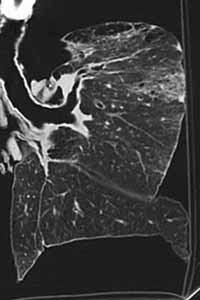

煤工塵肺2.X線檢查煤工塵肺胸片表現特徵有:網狀改變;結節狀改變;結節融合;塊狀陰影和多量絨毛狀改變。網狀改變被認為是煤工塵肺最早的表現,在肺野呈現瀰漫性細網狀陰影。而此時在臨床上無任何症狀。隨著結節的擴展,病變融合成不透明的進行性大塊纖維化,通常位於兩肺上野,也可跨肺葉融合至中、下肺野,有時僅發生在一側肺野,通常為大塊狀,均勻的、界限明顯的陰影。這些改變往往在單純性煤工塵肺彌散結節陰影的背景上發生。

伴有類風濕性關節炎的煤工塵肺患者,即Caplan綜合徵的胸部X線片往往呈現多個圓形、邊界清晰、分布較均勻的結節。在雙肺甚至分布至肺野周圍部分。圓形結節直徑可從0.5~5cm,但通常為1cm左右。有時病變出現與關節炎並無明顯相關性,或開始出現關節炎後病情迅速發展。在Caplan肺部病變可出現中心空洞,鈣化以及病變融合現象。在進行性大塊纖維化患者或有重度吸菸史者多合併有肺氣腫,嚴重肺氣腫往往致使肺部點狀和小結節顯示不清,易導致臨床醫生對病變